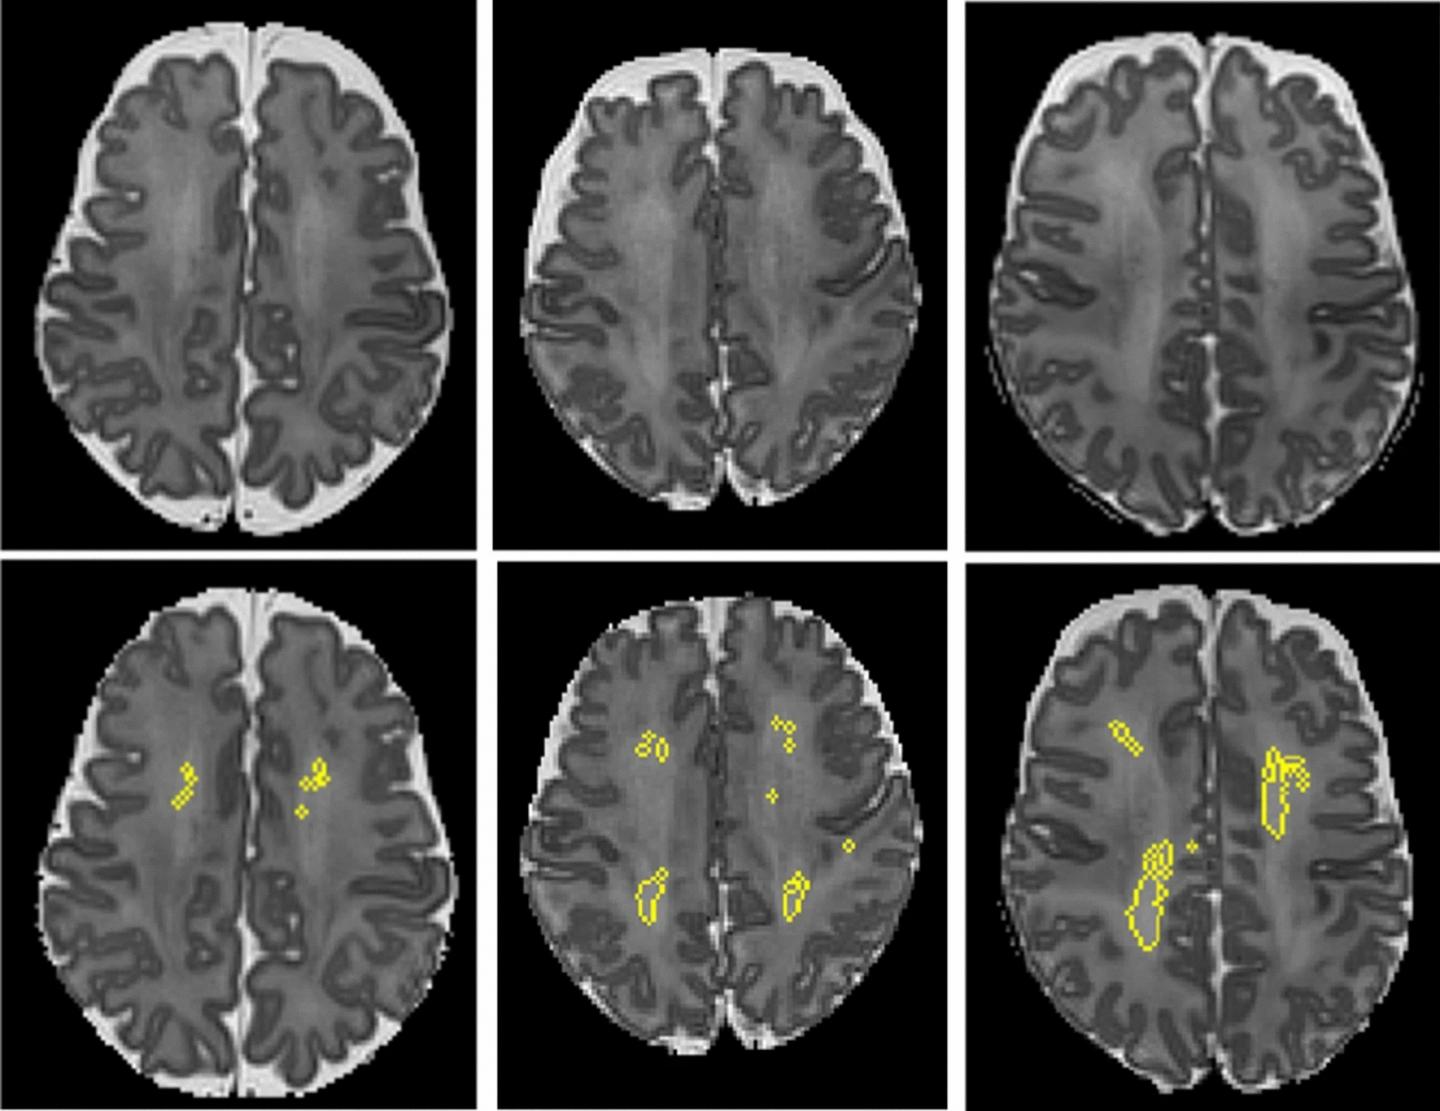

image: These MRI scans show diffuse white matter abnormality (DWMA). The top three panels display raw MRI images from very preterm infants born at 27 weeks (left), 26 weeks (center) and 31 weeks (right) gestation. Higher signal intensity can be seen in the central white matter, particularly for the 31-week gestation infant. The bottom panels display the corresponding slices with objectively segmented DWMA in yellow. The 27-week infant (left) was diagnosed with mild DWMA, the 26-week infant (center) was diagnosed with moderate DWMA, and the 31-week infant had severe DWMA. view more

Credit: Cincinnati Children's and Nature Scientific Reports